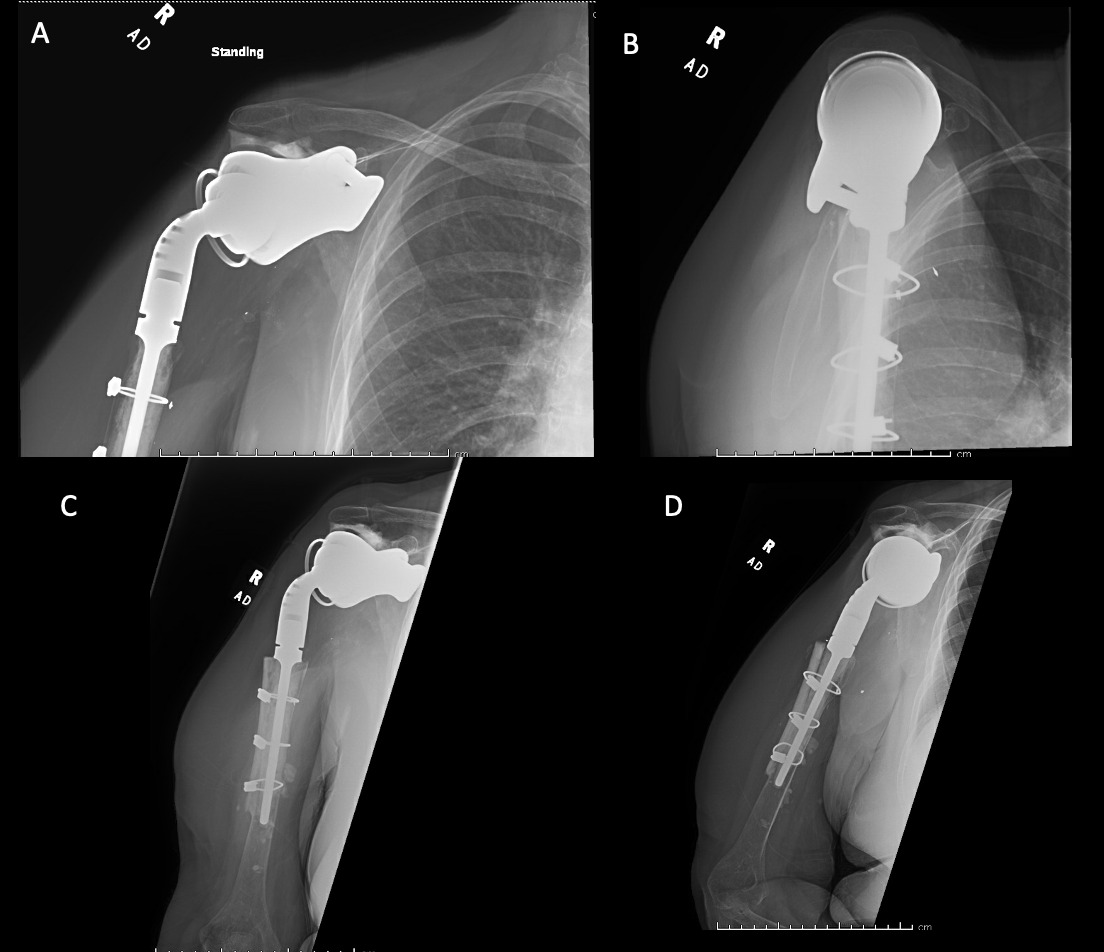

A 69-year-old woman presented after resection arthroplasty of her right shoulder hemiarthroplasty and completion of antibiotic treatment for culture negative PJI for evaluation of reconstructive options. She had a history of a displaced two-part right proximal humeral fracture which was repaired with an intramedullary nail. Post operatively, she had persistent pain and CT scan of the shoulder showed two screws in the humeral head that extended through the cortex and into the glenohumeral joint. The screws were removed and replaced with smaller screws. Subsequently, she had non-union of the fracture in the setting of deltoid weakness and was revised to a right hemiarthroplasty (Figures 1-3). Post operatively, she had persistent pain refractory to physical therapy and diminished function that was impacting her quality of life. She sought subsequent care, and there was concern for arthroplasty failure secondary to a septic versus aseptic condition and the decision to proceed with resection arthroplasty was made. During resection arthroplasty, a significant amount of fluid was expressed from the joint space. The combination of the clinical picture of progressive and persistent pain and the gross expression of fluid were concerning for PJI and the decision to treat was made. It was felt that the extent of humeral bone loss did not allow for a stable cement spacer, so none was placed. Intraoperative joint fluid cultures, anaerobic, and fungal cultures were all negative for growth. Cultures were held for 21 days to rule out C. Acnes infection. Considering the plan for future reimplantation, infectious disease consultation recommended a 6-week course of vancomycin but after 2 days the patient had a transfusion reaction and was switched to daptomycin. She was left with markedly limited active motion associated with severe pain. After completion of the antibiotic course, the patient elected to proceed with revision surgery. This patient had a flattened and distorted glenoid and atrophied rotator cuff musculature demonstrated prior to resection arthroplasty on CT (Figure 4). This patient’s prior hemiarthroplasty had been a tantalum coated, cemented humeral stem with associated marked thinning of the humeral cortex even prior to resection arthroplasty, and this resulted in a large amount of proximal humeral bone loss during the resection (Figure 5). The patient was severely debilitated by the right shoulder and wanted to proceed with reconstruction. Because of the combination of glenoid and humeral bone loss and the lack of rotator cuff attachments, a custom constrained prosthesis design process was initiated, and the implant was available 16 months after the resection arthroplasty. Preoperative 3 phase SPECT (Single Photon Emission Computed Tomography) three phase bone scan, upper extremity CT, and blood work (WBC 5.4, ESR 9, CRP 0.8) showed no suggestion of active infection.

A 62-year-old woman presented for evaluation of her reconstructive options after resection arthroplasty of a right rTSA and completion of antibiotic treatment for culture negative PJI. Her rTSA had been an Encore prosthesis placed due to rotator cuff arthropathy (Figures 6). Post-operatively she had persistent pain, stiffness, and tenderness to palpation that was treated with physical therapy, a steroid injection, and manipulation under anesthesia. An infectious work up due to the chronic and persistent nature of the pain showed WBC 7.4, ESR 53, CRP 1.2. Patient denied further work up with a tagged white cell scan and preferred continued clinical monitoring to observe pattern of symptoms. Eleven months later, she endorsed persistent pain. Repeat infectious work up showed WBC 4.5, ESR 13, and CRP 1.1. Despite the normal inflammatory markers, a 10-day trial of Augmentin was initiated and failed to change her symptoms. The decision to proceed with 1 vs 2 stage reconstruction was made. During resection arthroplasty, a substantial amount of fluid was expressed from the joint capsule concerning for PJI. A cement spacer was placed, and the patient was treated with 6 weeks of vancomycin and cefepime (Figure 7). There was proximal humeral bone loss as the result of resection arthroplasty due to the humeral stem. The glenoid component was loose and associated with glenoid bone loss, further complicated by the need for removal of a broken central screw (Figure 8).